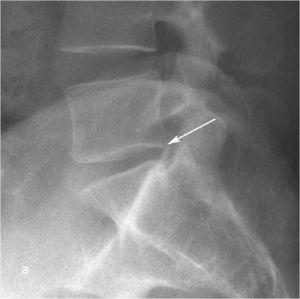

При рентгенографии (Рис.7) и МРТ (Рис.8) поясничного отдела позвоночника выявляется дегенеративный ретролистез L5 позвонка, секвестрированная парамедианная грыжа мп диска L5-S1 слева.

| Рис. 7а,b. Рентгенограмма поясничного отдела позвоночника в боковой (а) и прямой (b) проекциях до операции. Стрелкой показано смещение тела L5 позвонка кзади. | |

Пациенту выполнено оперативное лечение: удаление секвестрированной парамедианной грыжи мп диска L5-S1 слева из минидоступа, миниинвазивная транспедикулярная фиксация L5-S1 титановой конструкцией.

При контрольной рентгенограмме отмечено правильное положение транспедикулярной системы и кейджа на уровне L5-S1 позвонков. (Рис.9)